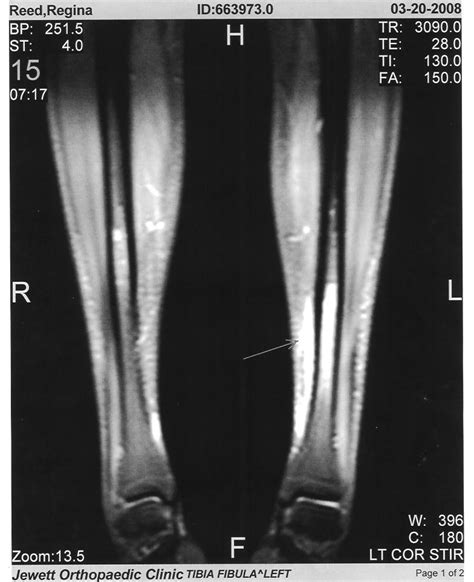

- Imaging studies such as X-rays, CT scans, or MRI scans may be necessary to confirm diagnosis

Diagnosing a stress fracture in the shin can be challenging, as the symptoms may be similar to those of other conditions such as shin splints or medial tibial stress syndrome. Imaging studies such as X-rays, CT scans, or MRI scans may be necessary to confirm the diagnosis. Treatment options for stress fractures in the shin typically include rest, ice, compression, and elevation, as well as physical therapy and orthotics to address any biomechanical factors that may be contributing to the injury.